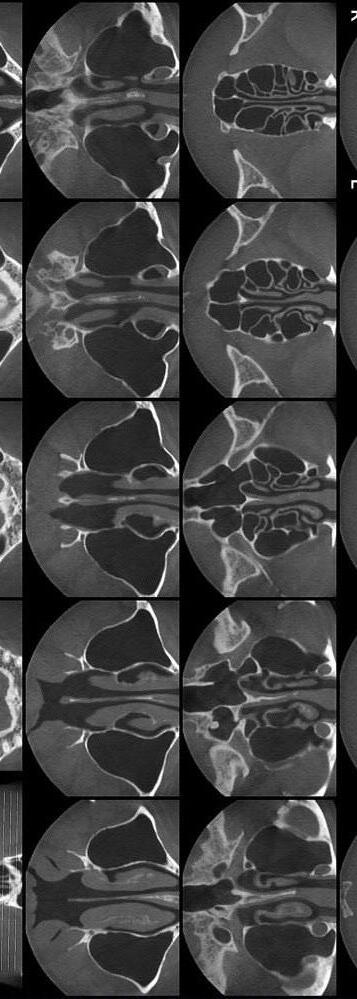

Ринопластика – це операція, проведення якої зумовлено

необхідністю змінити пропорції та контури носу, усунути деформації. Операція

носить в собі як косметичнийхарактер,такіможебути

спрямована на відновлення

носового дихання та корегування носової перегородки.

Є три основні види рино-

пластики:

•Реконструктивна – це опе-

рація, яка спрямована на

корегування перегородки

носу і відновлення дихаль-

ної функції. Включає в себе

загальне втручання в ана-

томіюносу;

•Косметична – це операція, яка спрямована на зміну зовнішнього вигляду носу.

В такому випадку корегу-

ютькінчик,крилачиносові

раковини;

•Безопераційна–цеопера-

ція, яка передбачає корегування форми за допомогоюін’єкцій.

Існуєдваметодипроведен-

няринопластики:

• Закритий – малоін-

вазивна процедура, яка проводиться всередині

носової порожнини, без пошкодженняшкіри;

• Відкритий – спосіб, який використовують для істотнихзмінпридеформаціяхіпатологіях.